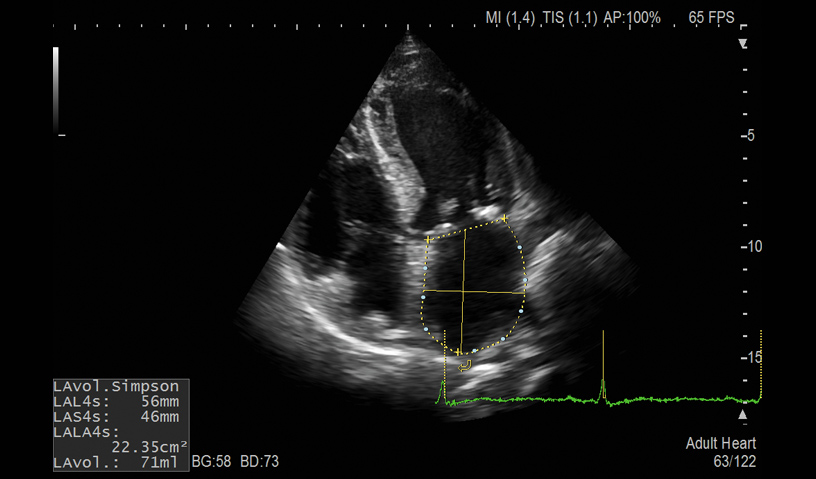

LA Volume

- Auto LV, LA and RA Volume and FAC